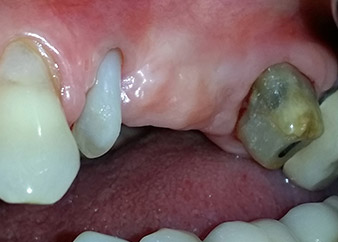

Un mes después, en el día de la intervención, el dolor y la inflamación se habían reducido al mínimo en la pieza 24, pero seguía habiendo una movilidad de clase II de Miller. Después de la apertura de los colgajos y de la limpieza del tejido infectado periapical y perirradicular, la extensión del defecto óseo quedó evidente (figuras 2 y 3).

En la raíz bucal, faltaba todo el hueso vestibular y distal. Básicamente, la fijación se limitó a la raíz palatal, lo que corroboró el mal pronóstico preliminar. La pieza 27 también mostró una fijación horizontal reducida (figura 12) y una rarefacción apical mínima (figura 1), si bien sin síntomas clínicos.